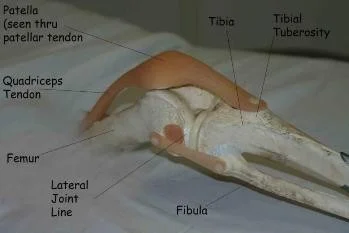

- Bone: landmarks (Patella, Tibial Tuberosity, head of Fibula) tenderness, mass, crepitus

- Joint lines: anterior, medial, lateral

- Joint assessment: swelling, effusion, crepitation, synovial thickening, joint line tenderness